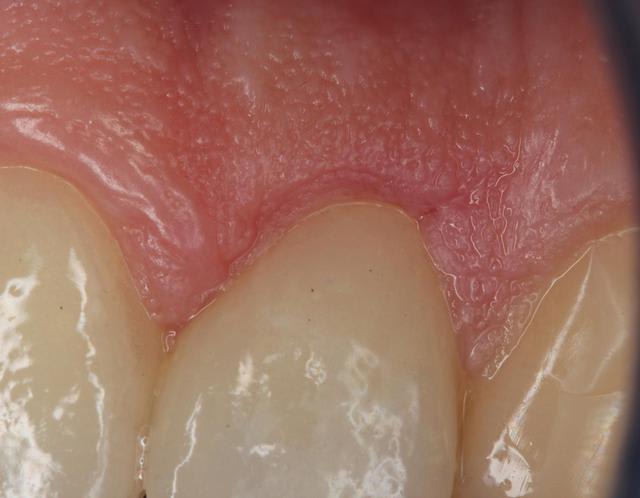

pour faire suite à ce cas, et montrer l’intégration gingivale, voici des photo a 1 mois.

ben elle est pas moche, ma GA!

Il est vrai que si tu as bien géré ton profil d'émergence la gencive ne remontera pas MAIS comme ta photo terminale en témoigne => Gingivite entre 22 et 21 ( exactement la ou la gingivectomie est la plus profonde ).

faudra m'expliquer où tu vois une gingivite entre 21 et 22?

non, mais t'as vu la qualité de la GA? faut pas déconner!

pour l'espace biologique, il va bien: sur 22, qui était en retrait, j'avais un wagon en GA . De +, je ne sais pas si vous avez déjà vu une gencive avec un espace bio insuffisant, mais en général, ça ne pardonne pas et est visible immédiatement.